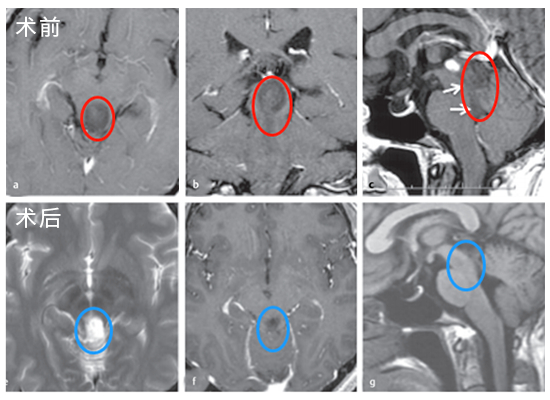

3. “一台手术,双入路”精妙手术创造15年生存希望

45岁的张先生突然遭遇剧烈头痛、喷射状呕吐,很快陷入意识模糊——这是颅内压急剧升高的危险信号!医生立即为他实施神经内镜下脑室造瘘术,暂时缓解了这场生死危机。

进一步检查发现更严峻的挑战:脑干肿瘤已从“生命中枢”向上侵袭至第四脑室。如果从小脑上部进入,手术深度难以超过2厘米,想要全切肿瘤几乎是不可能的任务!

面对这一“手术禁区”,巴教授采用“一台手术,双入路”的精准策略。通过多方位精准打击,在保护神经功能的同时,实现了肿瘤的最大程度切除,为患者赢得了生存希望!

手术入路图解

术后MRI

术后病理显示形成菊形团的胶质神经元肿瘤(RGNT),这位男士术后随访已达15年!